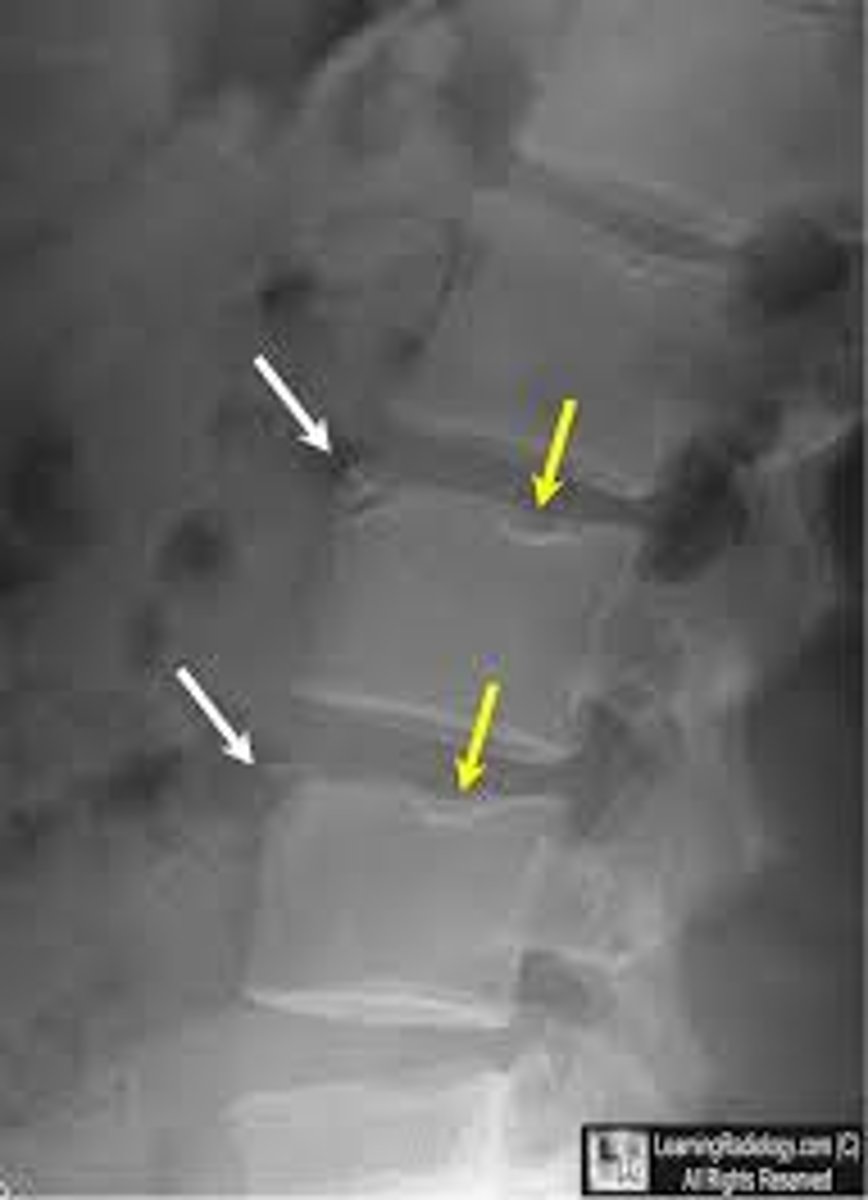

spondylolysis

fracture of pars interarticularis

spondylolisthesis

the forward slipping movement of the body of one of the lower lumbar vertebrae on the vertebra or sacrum below it

scottie dog sign

normal appearance of the lumbar spine in an oblique radiograph

*fracture occurs at the "collar"